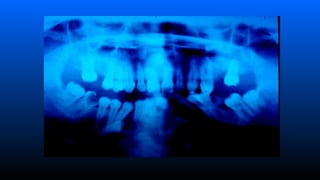

Tumores Odontogênicos

■ Odontomas complexos e compostos

– Freqüência 50 % dos T.Odontog.

– Localização Mol-mand (Complexo)

Ant-max (Composto)

– Clínica Pouca deformidad,e tumefação no rebordo, Retenção

de dentes.

– Radiología Lesão radiolúcida associada a área radiopaca + o

– semelhante a dentículos (O. composto) ou massa opaca (O.

complexo).

– Tratamiento Enucleação - rara recidiva